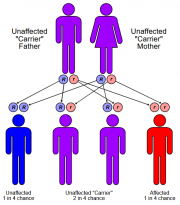

| 17:09, 27 בנובמבר 2017 | גנטיקה.jpg (קובץ) |  |

170 קילו־בייטים | דנה לוי | 1 | |